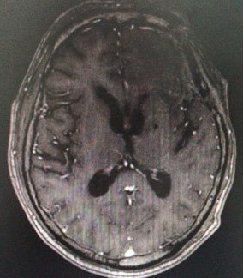

查头颅增强MR(2017-10-27,本院):示左侧额叶异常信号,考虑转移

增强T1:

头颅MRI(2018-02-08,本院)左侧额叶、叶脑软化灶;左侧基底节区慢性脑梗死;双侧额叶、右侧颈叶、左侧基底节区缺血性改变;老年性脑改变;右侧乳突炎

2019-11-05 脑MRI脑灌注:左侧额叶脑转移瘤术后,术区灌注参数(ASL、PWI)较对侧减低,暂不考虑转移或复发。